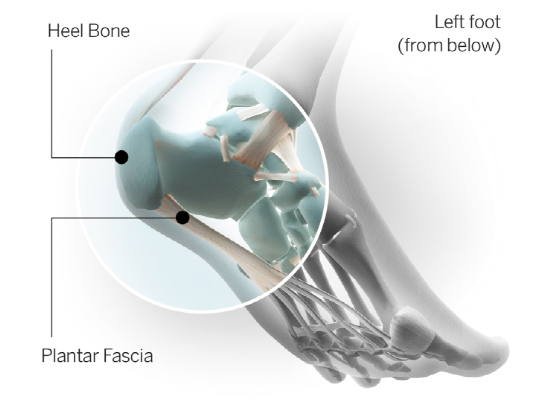

什么是足底筋膜?

人的脚是由众多足骨所构成的一个拱形构架,这种拱形结构连同脚底多层软组织(脂肪垫、筋膜)构成了足弓。

足弓可以发挥很好地适应地面,缓冲足着地时的撞击力、避免足底血管神经免受压迫等作用。

足底筋膜就是位于足底的软组织,它起自脚跟处的跟骨,向前止于脚趾,由于脚趾头有五个,足底筋膜向前分叉为五束,足底筋膜的主要功能是缓冲,同时也协助维持足弓。